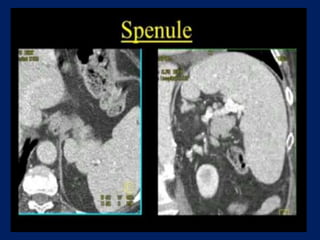

This document discusses imaging of the spleen and summarizes various congenital anomalies and pathologies that can affect the spleen. Some common congenital anomalies mentioned include accessory spleens, asplenia, polysplenia, and splenic fusions. Acquired conditions like repeated infarctions, infiltration, tumors, and cysts can also cause splenomegaly or functional asplenia. Wandering spleen is discussed as a rare congenital anomaly where the spleen lacks attachments and is mobile within the abdomen. Various grades of splenic lacerations and examples of splenic imaging findings are also briefly summarized.